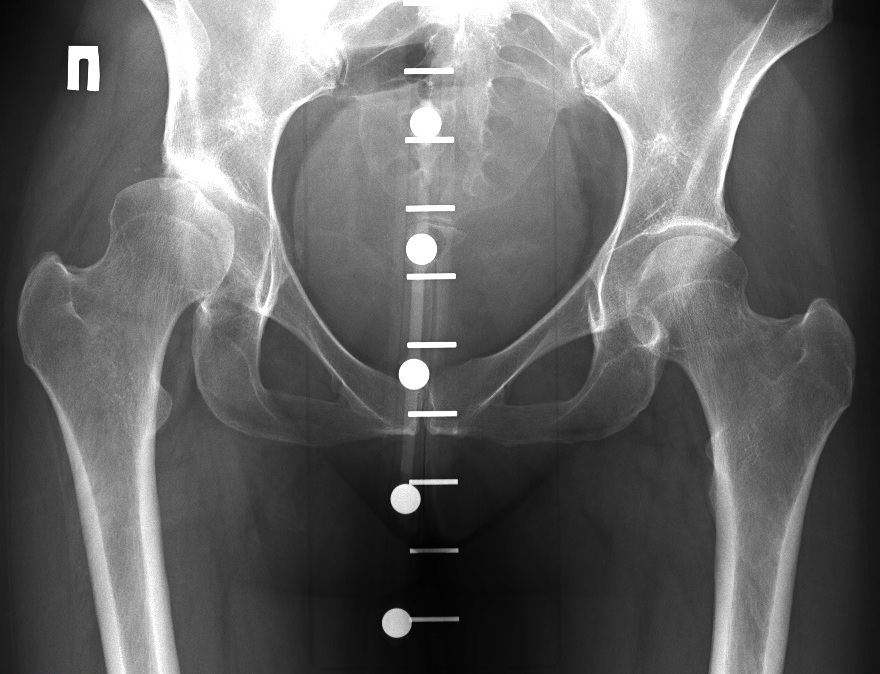

Клинический наблюдения и методы. Под нашим наблюдением с 2008г. по настоящее время находилось 172 пациента с коксартрозом 1-2 стадии в возрасте от 26 до 72 лет, с давностью заболевания от 1 до 20 лет. Мужчин было 51 (30%), женщин 121 (70%).

У 674 пациентов (43 %) отмечено сочетание коксартроза с остеохондрозом. Двухстороннее поражение тазобедренных суставов наблюдалось в 29% случаев.

Для своевременного выявления ранних проявлений коксартроза нами применяется комплексный подход в диагностике данной патологии, включающий: опрос, осмотр сустава, проверка объема движения в нем, рентгенографию, компьютерную томографию (КТ), магнитно-резонансную томографию (МРТ) и ультразвуковое исследование (УЗИ) тазобедренного сустава.

На рентгенограммах тазобедренный сустав сохраняет нормальную форму, суставная щель умеренно или неравномерно сужена с субхондральным склерозированием костных суставных поверхностей, непостоянными краевыми костными разрастаниями (I стадия).

Рентгенологически суставная щель может быть равномерно или неравномерно сужена, ацетабулярная суставная впадина уплощена, присутствуют явления субхондрального склероза, краевые костные разрастания. Конфигурация головки бедренной кости, как правило, не нарушена (II стадия).

В подавляющем большинстве случаев диагноз коксартроза ставится при рентгенографии, где видны изменения формы и структуры костей, составляющих тазобедренный сустав. Однако рентгенографически в ряде случаев затруднительно зафиксировать ранние проявления артроза, так как хрящевая ткань суставных поверхностей на рентгеновских снимках не отображается и мы можем судить о дегенеративном процессе, когда он достаточно выражен, вызывая изменения ширины просвета рентгеновской суставной щели.

Выводы. Таким образом, учитывая доступность и экономическую целесообразность, скрининговыми методами диагностики коксартроза являются рентгенография и УЗИ тазобедренных суставов. При несоответствии клинической картины и данных методов исследования необходимо КТ и (или) МРТ, что позволяет повысить качество диагностики и назначить адекватную терапию.